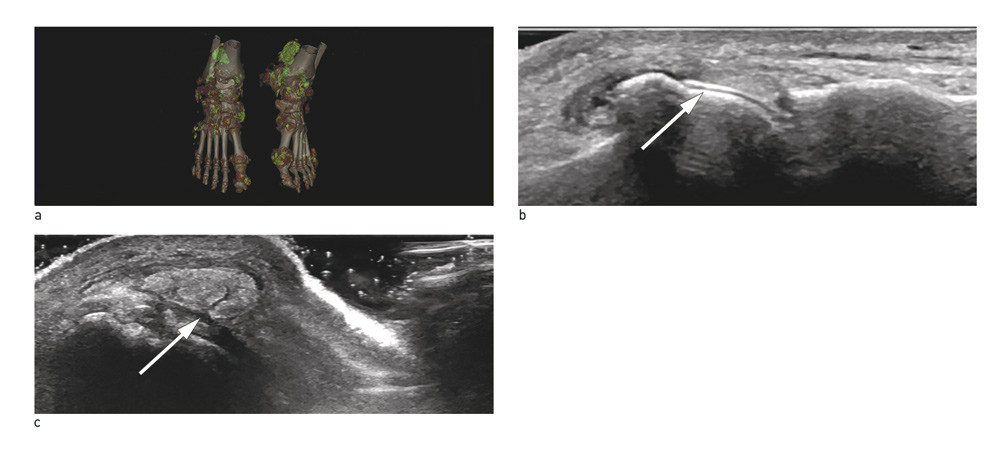

Ultralydundersøkelse brukes i økende grad av revmatologer for å diagnostisere forskjellige degenerative og inflammatoriske revmatiske sykdommer. Ved et internasjonalt samarbeid er det nå identifisert fire ultralydforandringer som angis å være typiske for urinsyregikt (10).

Dobbelkontur. En hyperekkoisk linje på overflaten av brusken reflekterer massiv avleiring av urinsyrekrystaller. Konturen er diagnostisk når den påvises på bruskoverflaten i en vinkel som ikke er 90° på ultralydproben (dvs. ikke vanlig bruskrefleksjon). Konturen har typisk samme tykkelse som konturen av benoverflaten, derav navnet dobbeltkontur (som dannes av en hyperekkoisk (hvit) benoverflate over den en anekkoisk (svart) brusk og øverst en hyperekkoisk (hvit) urinsyrekrystallavleiring på bruskens overflate) (fig 1).

Tophus. En tett samling av urinsyrekrystaller som kan ses inne i et ledd, inne i en sene eller seneskjede, subkutant eller i øvrig vev. Disse avleiringene kan være myke, dvs. man kan se bevegelsene til urinsyrekrystallene inne i tophus ved palpasjon, eller harde, dvs. med forkalkninger som gir slagskygge. Størrelsen varierer fra millimeterstore til flere centimeter store (fig 1).

Påvisning av dobbelkontur og tophus vil være diagnostisk for urinsyregikt, selv om påvisning av urinsyrekrystaller er ønskelig ved leddpunksjon (som kan utføres ultralydveiledet for bedre muligheten til å aspirere krystallholdig væske/vev).